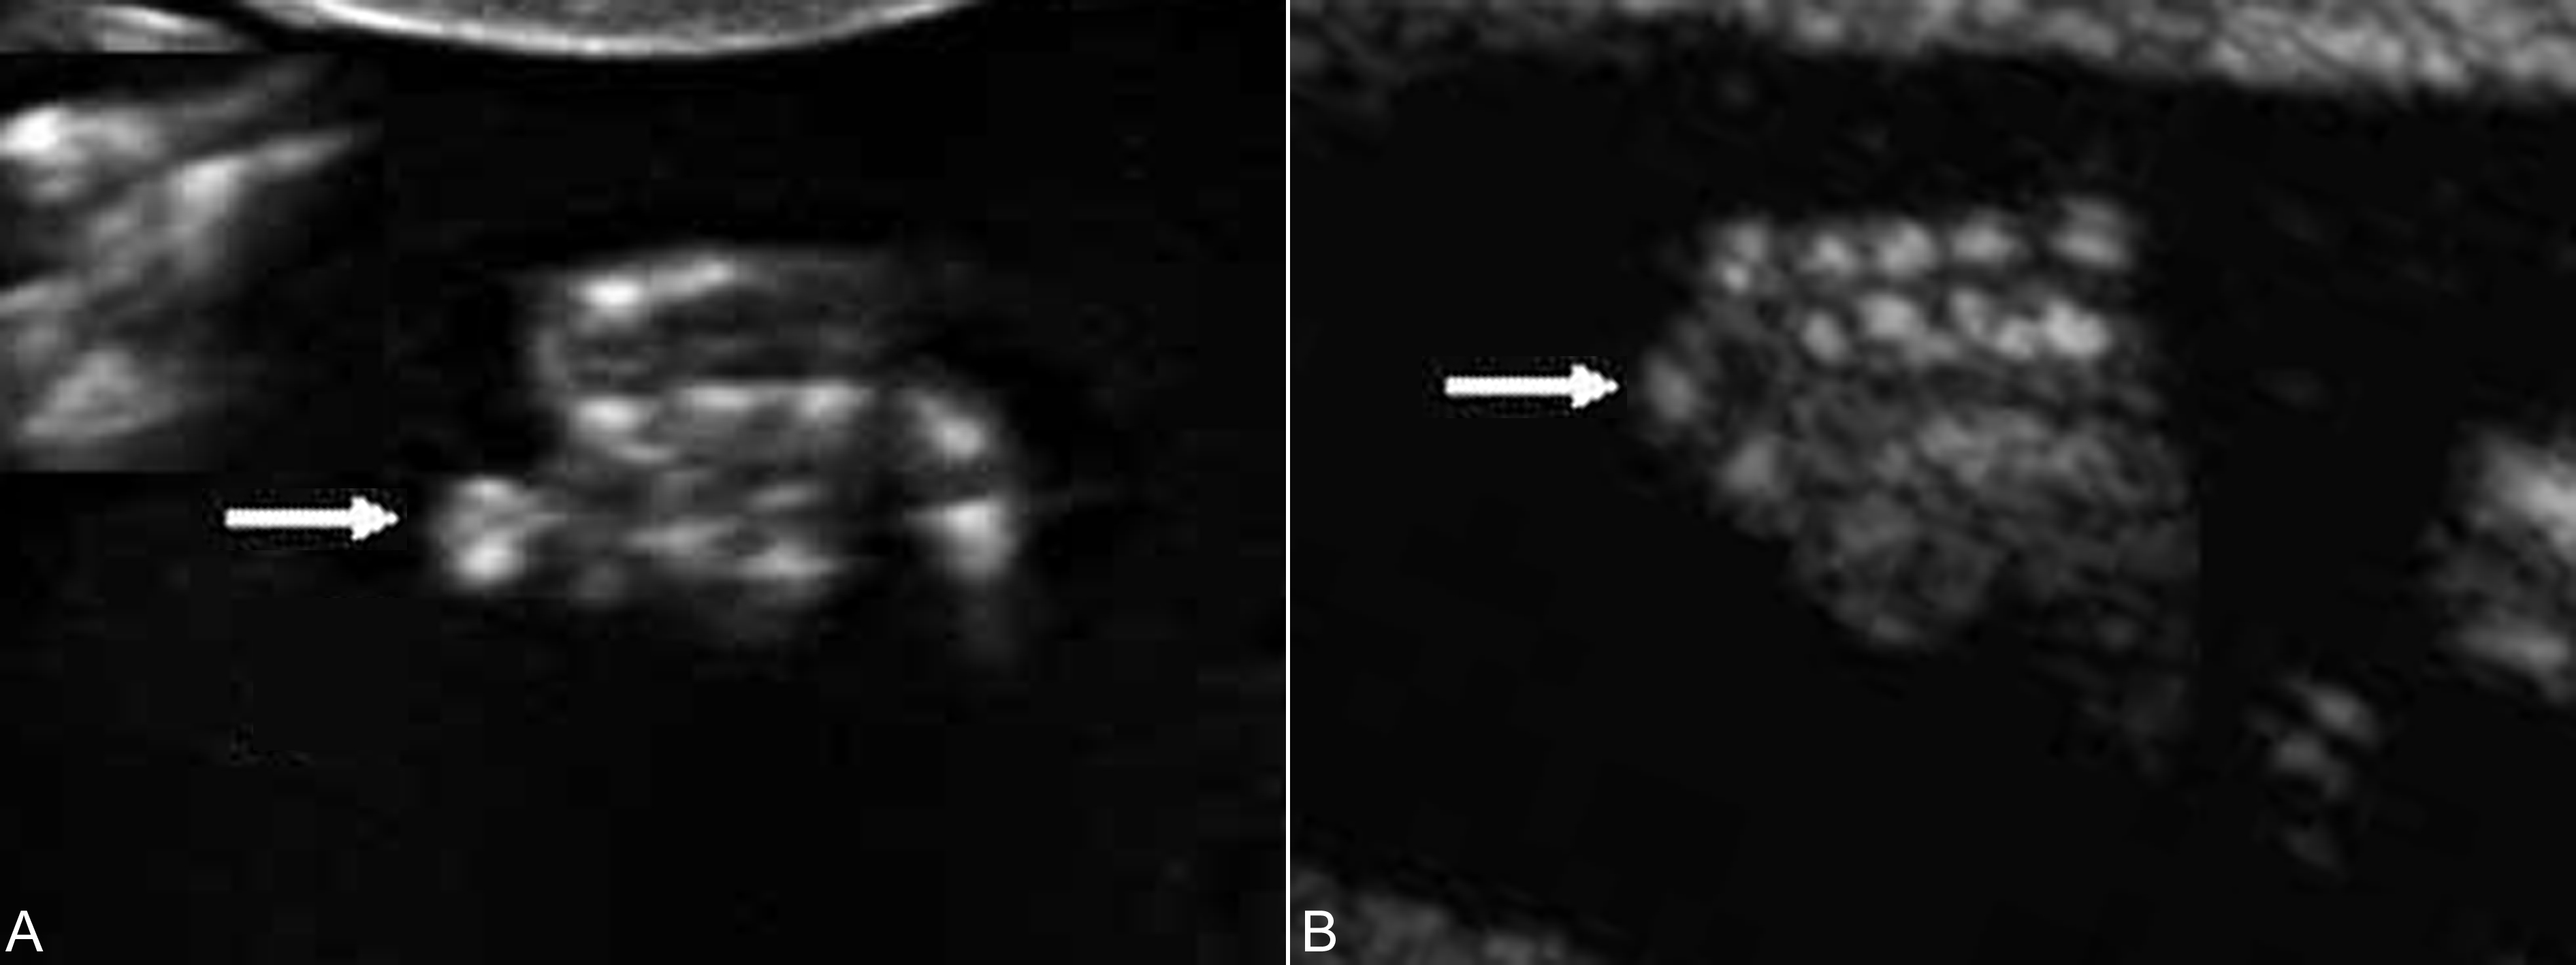

手(足)指(趾)的侧方的重复畸形,包括轴前型和轴后型多指(趾)畸形时,手(足)指(趾)的正常形态多可显示,仅仅是在手的一侧显示额外的回声,多数结构异常或骨骼短小,与正常的手指排列关系明显不一致,较短,指(趾)骨缩短或有弯曲,与相邻指(趾)骨或掌(跖)骨成角畸形(图3,图4)。如果不能显示手(足)指(趾)的正常形态并且指(趾)数增多,则为中央型多指(趾)畸形。显示中央型多指(趾)畸形时需要注意观察多指(趾)与邻指(趾)的关系,如果表面皮肤及皮下软组织完整,则为多指(趾)并指(趾)畸形。产前超声检查发现多指畸形后要注意胎儿头部、胸部、心脏及腹部的检查(图5),发现有无合并的畸形对预后的评估非常重要。

图3轴后型多指二维超声显像检查(A)及三维维超声检查(B)显示突出的多指(箭头)